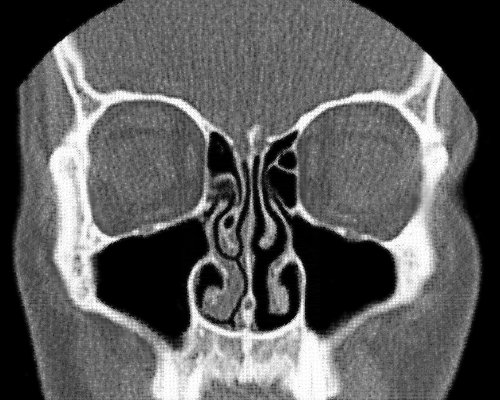

وفي الأشعة المقطعية يتطلب ظهور التضخم الفعلي للقرينيات بقاء المريض مستلقيا على لوح الأشعة عدة دقائق قبل إجرائها. ولهذا إذا تم إجراؤها بسرعة قد لا تظهر القرينيات بتضخمها الحقيقي الذي يتسبب في معاناة المريض، وبالتالي يكتب طبيب الأشعة في التقرير أن حجم القرينيات طبيعي.